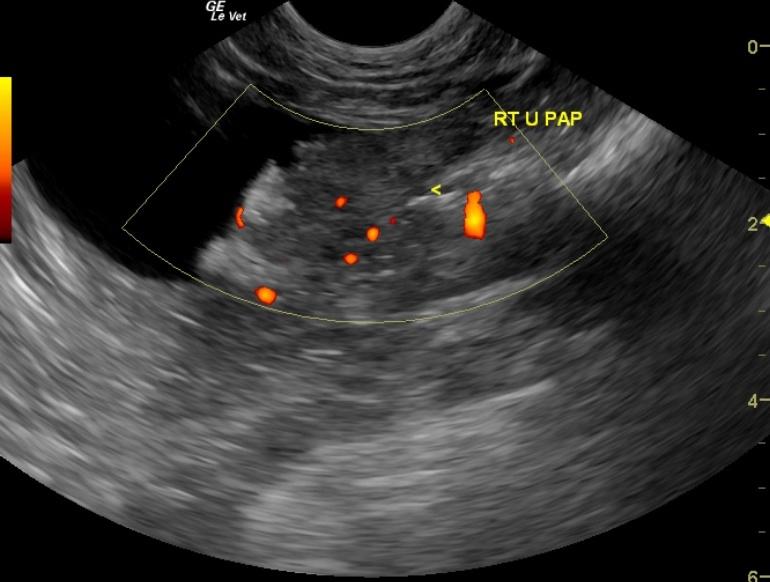

The urinary bladder contained a 3.3 x 1.34 cm mineralizing mass located at the dorsolateral aspect of the bladder and encroaching on the right ureteral papilla. Slight renal pelvic dilation was noted in the left kidney with moderate dystrophy and fibrosis. The right kidney was severely fibrosed and measured 2.7 cm.

BladdermassLeftureteralpapillaRightureteralpapilla